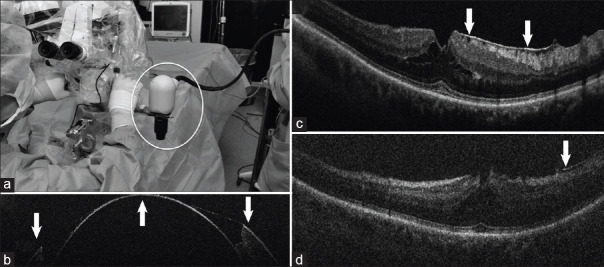

Intraoperative optical coherence tomography (iOCT) offers valuable real-time, depth-resolved visualization of ocular anatomy and during ophthalmic surgical maneuvers, which can be used to augment clinical decision-making, help verify surgical endpoints, enhance surgical precision, and facilitate the development of novel surgical techniques. Early iOCT demonstrations used perioperative devices, such as handheld and intraocular probes, which required pauses in surgery and disrupted clinical workflow. The advent of microscope-integrated systems addressed these limitations, allowing for iOCT imaging concurrent with surgical microscopy. iOCT image visualization has similarly progressed from external monitors, which require surgeons to divert their gaze, to heads-up displays integrated into microscope oculars, enabling direct overlays and improved ergonomics. Most recent advances have included increasing imaging speed to enable four-dimensional visualization of surgical dynamics and integration of automated surgical instrument tracking technologies. Clinical translation of iOCT has demonstrated utility across a range of procedures, including glaucoma surgery, corneal transplants, cataract extraction, vitrectomy, membrane peel, retinal detachment and macular hole repair, subretinal injection, and retinal prosthesis placement. As more advanced technologies are integrated into the conventional ophthalmic surgical workflow, iOCT has the potential to improve surgical performance and patient outcomes.